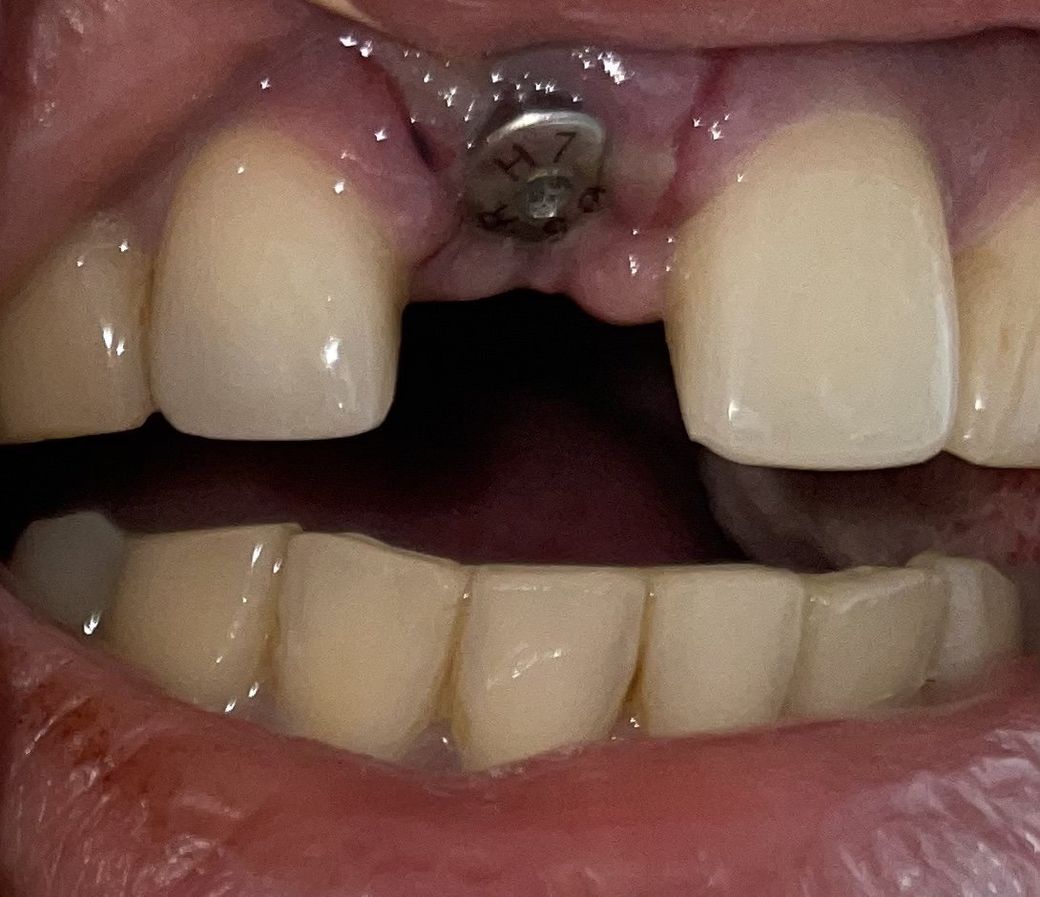

임플란트 실밥 제거 후 실밥이 남아있어요

상악 앞니와 우측 아래 어금니2군데 도요ㅣ에 임플란트 픽쳐스 식립 후 오늘 일주일째

집에 와서 거울을 보는게 검은 선이 보여서

혹시 실밥인가 하고 살짝 벌려보니 실밥 매듭이 보이네요…

사진으로 정확하게 찍히지는 않아요

저렇게 잇몸 사이에 실밥이 있으면 간혹 치과의사들이 놓치기도 하는데요,

감염의 통로가 될 수 있어서 3개월 기다시는게 아니라 가서 실밥을 뽑으시는게 좋습니다.

사진상으로 정확히 보이지 않지만,

만약 실밥이 남아있다면

다시 치과에 가셔서

실밥을 제거하고, 소독을 받는것이 좋습니다.

사진상으로는 실밥인지 아닌지 확실히 확인 안됩니다

만약 실밥이 확실하다면 치과에 내원하여 뽑아야 됩니다. 3개월 동안 그냥두면 안됩니다. 그전에 뽑아내야 합니다.

해당 사진으로는 실밥이 보이지 않습니다. 실밥이 잔류되어 있는 것은 회복에 좋지 않습니다. 따라서 실밥이 맞다면 다시 치과를 내원하여 실밥을 제거하는 것이 필요합니다. 엑스레이 상에서 임플란트 픽스쳐 식립은 잘되어 있습니다. 따라서 실밥 잔류되어 있는 것만 제거하시면 될 것 같습니다.

사진상으로는 실밥이 보이진 않습니다. 실밥처럼 보이는것은 잇몸절개라인이 그렇게 보이는것으로 보입니다.

만약 실밥이 남아있다면 꼭 제거하셔야합니다. 사진상으로 매듭이 보이지 않지만, 잇몸을 벌렸을때 매듭이 확실히 보인다면 치과에 한번 방문해보시기 바랍니다.